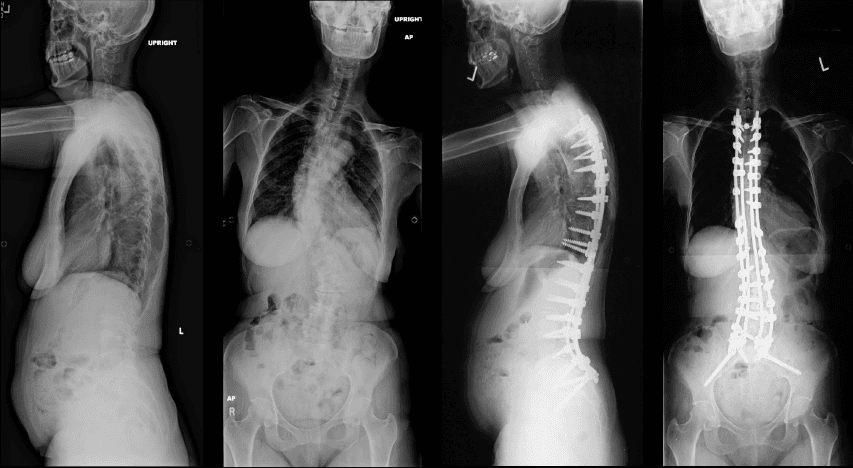

Adult spinal deformity (ASD) refers to an abnormal alignment or curvature of the spine that develops after skeletal maturity. It's often a progressive condition caused by age-related degeneration, which can lead to significant pain, physical imbalance, and reduced quality of life. It is characterized by a deviation of greater than 10 degrees from the normal straight alignment.

Surgical Treatment

Surgery is typically reserved for severe cases where non-surgical treatments have failed, or when the deformity is causing severe pain, neurological deficits, or a significant impact on quality of life.